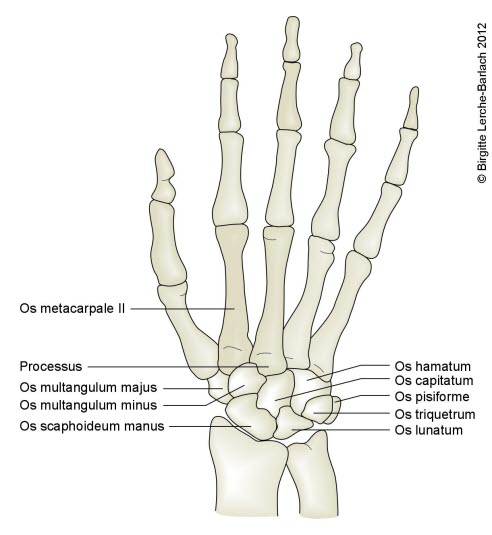

Mellomhåndsbenene, metakarpene, forbinder håndroten med hver av de fem fingrene. De nummereres fra tommelfingersiden til lillefingersiden - fra 1 til 5. Mellomhåndsbena danner ytterst ledd (MCP-leddet) med det innerste fingerbeinet og i den andre enden danner de ledd (CMC-leddet) med håndrotsbena (karpalbena). Det enkelte mellomhåndsbeinet består av to leddhoder og et langt skaft.